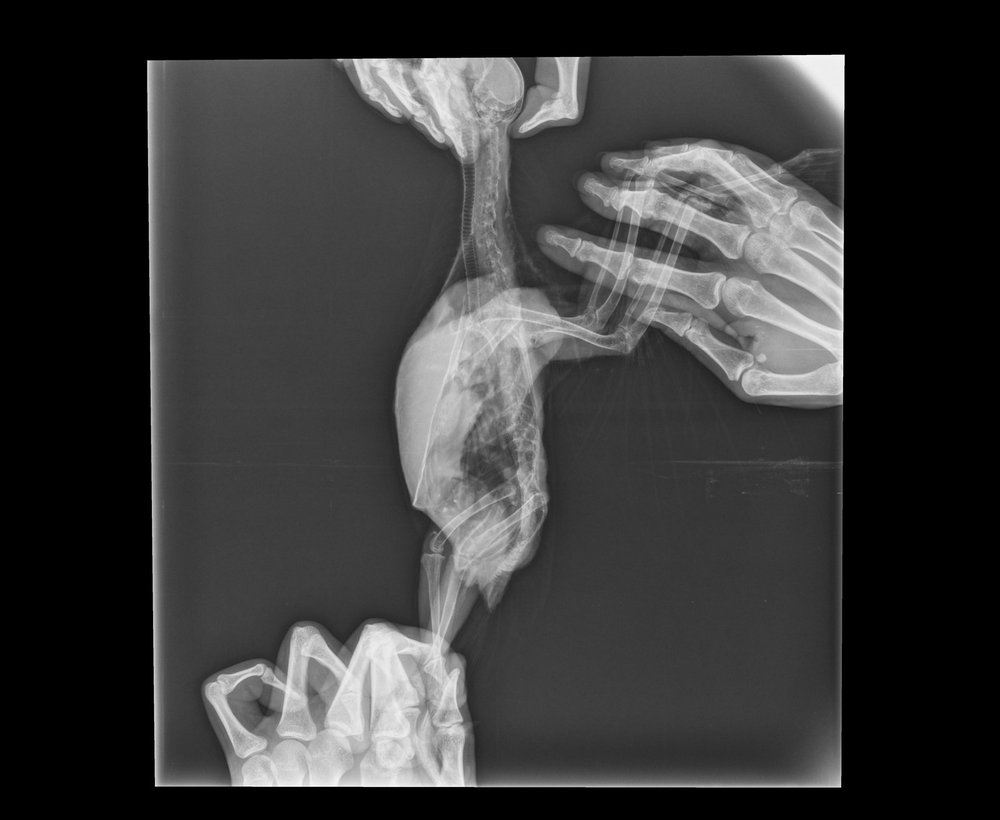

KamaRo Опубликовано 28 ноября, 2018 #8 Опубликовано 28 ноября, 2018 @Nadea про Аронову спросила, т.к. подумала, что она в декрете и сейчас прием не ведет. Аронова стажируется у Волгиной, что говорит о стремлении доктора постоянно расти. А с птицами всегда тяжело, много чего остается за нашим пониманием (не все виды исследований доступны, как у кошек/собак). Если вы у другого врача наблюдались, то о нем тоже хорошие отзывы не помешали, чтобы владельцев птиц направлять к специалисту. При сильном нарушении в работе органов, в т.ч. ЖКТ нужно препараты давать в клюв, с едой мало попадает по назначению. У вас и антибиотики были и довольно тяжелый для печени препарат - орунгал, поэтому лечить уже в комплексе нужно (и гепатопротекторы принимать, и про-пребиотики). Не плохо работают при нарушении микрофолоры - споровит+бифидо-и лактобактерии, фортифлора+бифидо-и лактобактерии, были не плохие результаты на энтероле+пробиотик. Просто какой то метод выбирают и дают в клюв. Споровит (в жидком виде) по 0,3 мл 2 раза в день, методом подбора лакто-и бифидосодержащий пробиотик (мне всегда нравился бифидумбактерин - там 5 доз, на волнушку на глаз флакон делила на 8 приемов, шпажкой откалывала, разводила водой и выпаивала), на амазона наверное 1/2 флакона на 2 приема (утро-вечер). Что касается гепатопроткторов, то их еще с месяц дают после противомикробных препаратов и тоже в клюв. Шрот расторопши в данном случае не особо помогут - это полезная добавка, но в качестве самостоятельного компонента не справится. Гептрал может быть на гепатовет заменить, но он жутко вонючий, но птицы его вполне не плохо переносят, особенно если на 2 приема разделить (но его нужно разводить, т..к суспензия густая и тяжело выпоить). Сейчас вам нужно восстанавливать птицу.